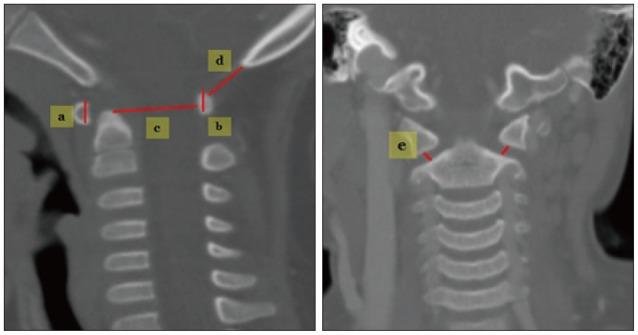

A total of 238 patients were included in this study, and mean age was 47.8±21.3 months. Spinal canal diameter, Power's ratio, McRae line, antero-posterior C1 ring height, atlantoaxial joint space, C2 growth, epidural space from the dens (M-PB-C2) and longitudinal distance (basion to C2 lower margin, B-C2) were measured. The mean value of each parameter was assessed for individual age groups. The cohorts were then divided into three larger age groups : infancy (I) (≤2 years), very early (VE) childhood (2-5 years) and early (E) childhood (5≥ years).

本研究共纳入238例患者,平均年龄为47.8±21.3个月。测量椎管直径、鲍尔氏比率、麦克雷线、C1环前后高度、寰枢关节间隙、C2生长情况、齿状突硬膜外间隙(M-PB-C2)和纵向距离(颅底至C2下缘,B-C2)。评估每个参数在各个年龄组的平均值。然后将队列分为三个更大的年龄组:婴儿期(I)(≤2岁)、极早期(VE)儿童期(2-5岁)和早期(E)儿童期(≥5岁)。